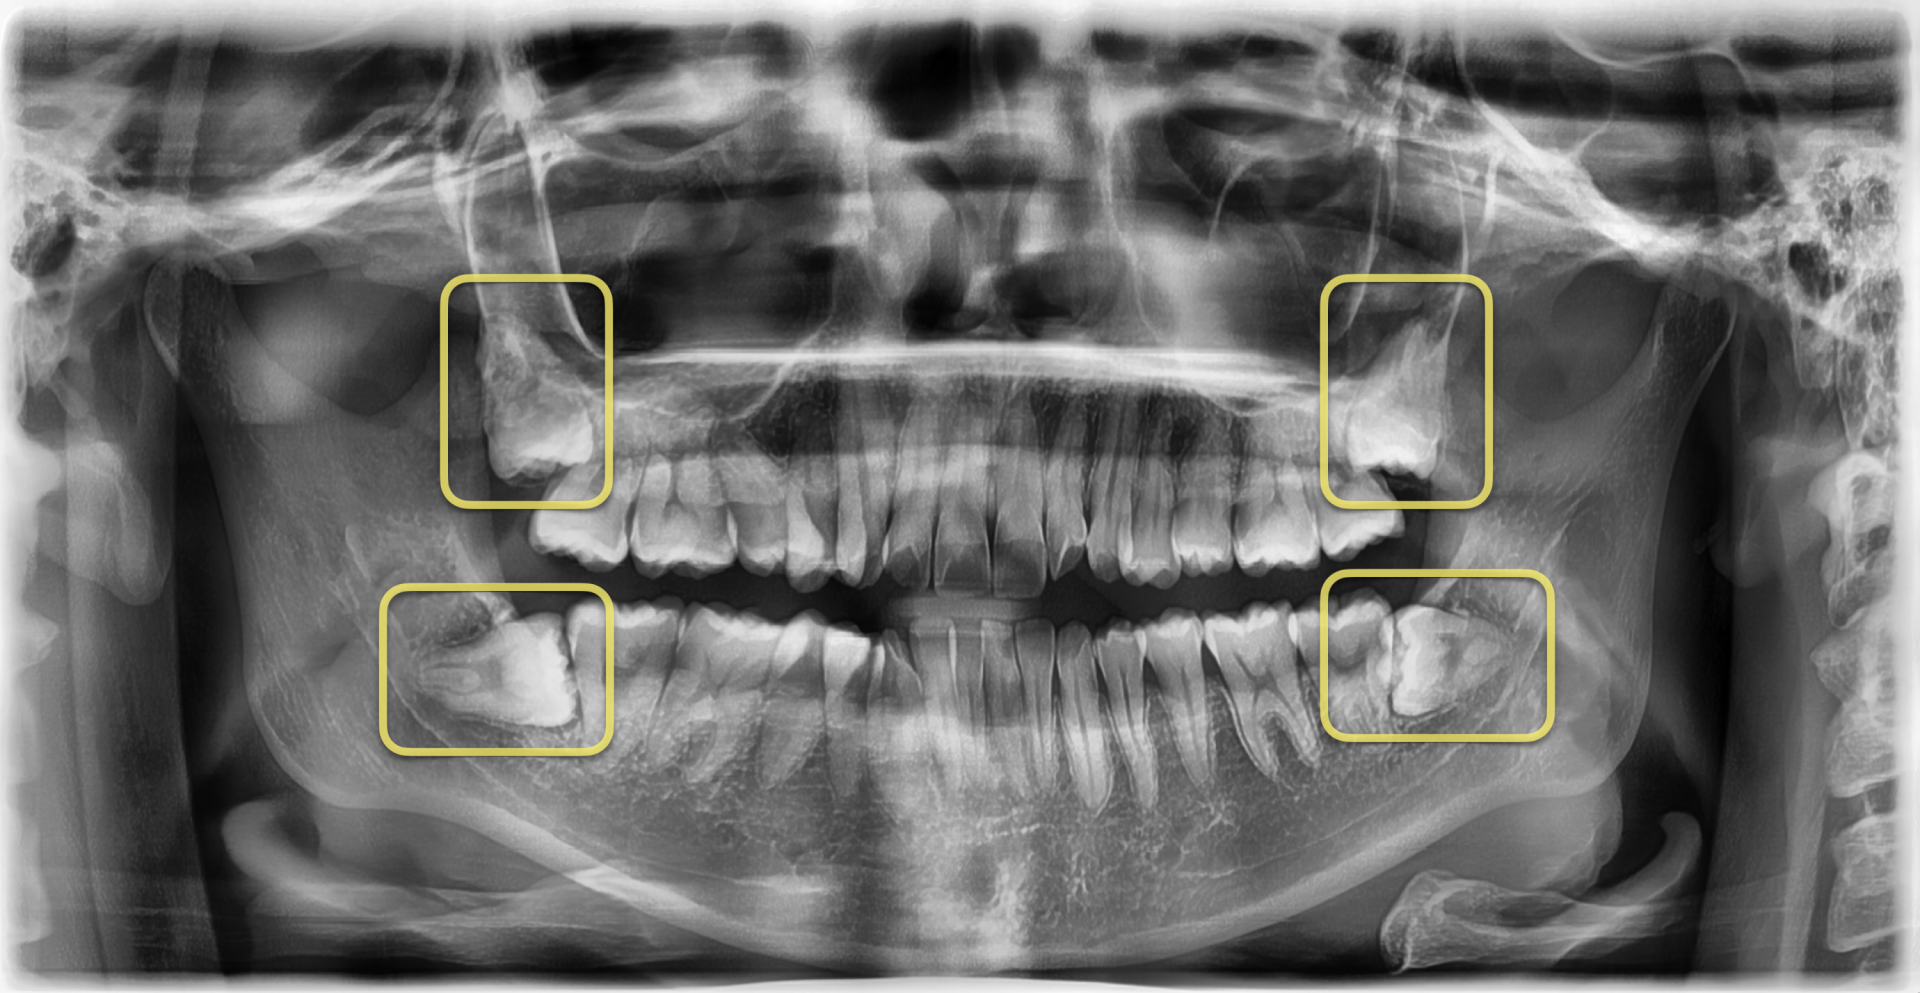

교정 치료를 위해

4개의 "매복" 사랑니를 전부 발치가 필요한 상황이셨고,

4개 모두 발치 난이도가 있는 케이스 였습니다....!